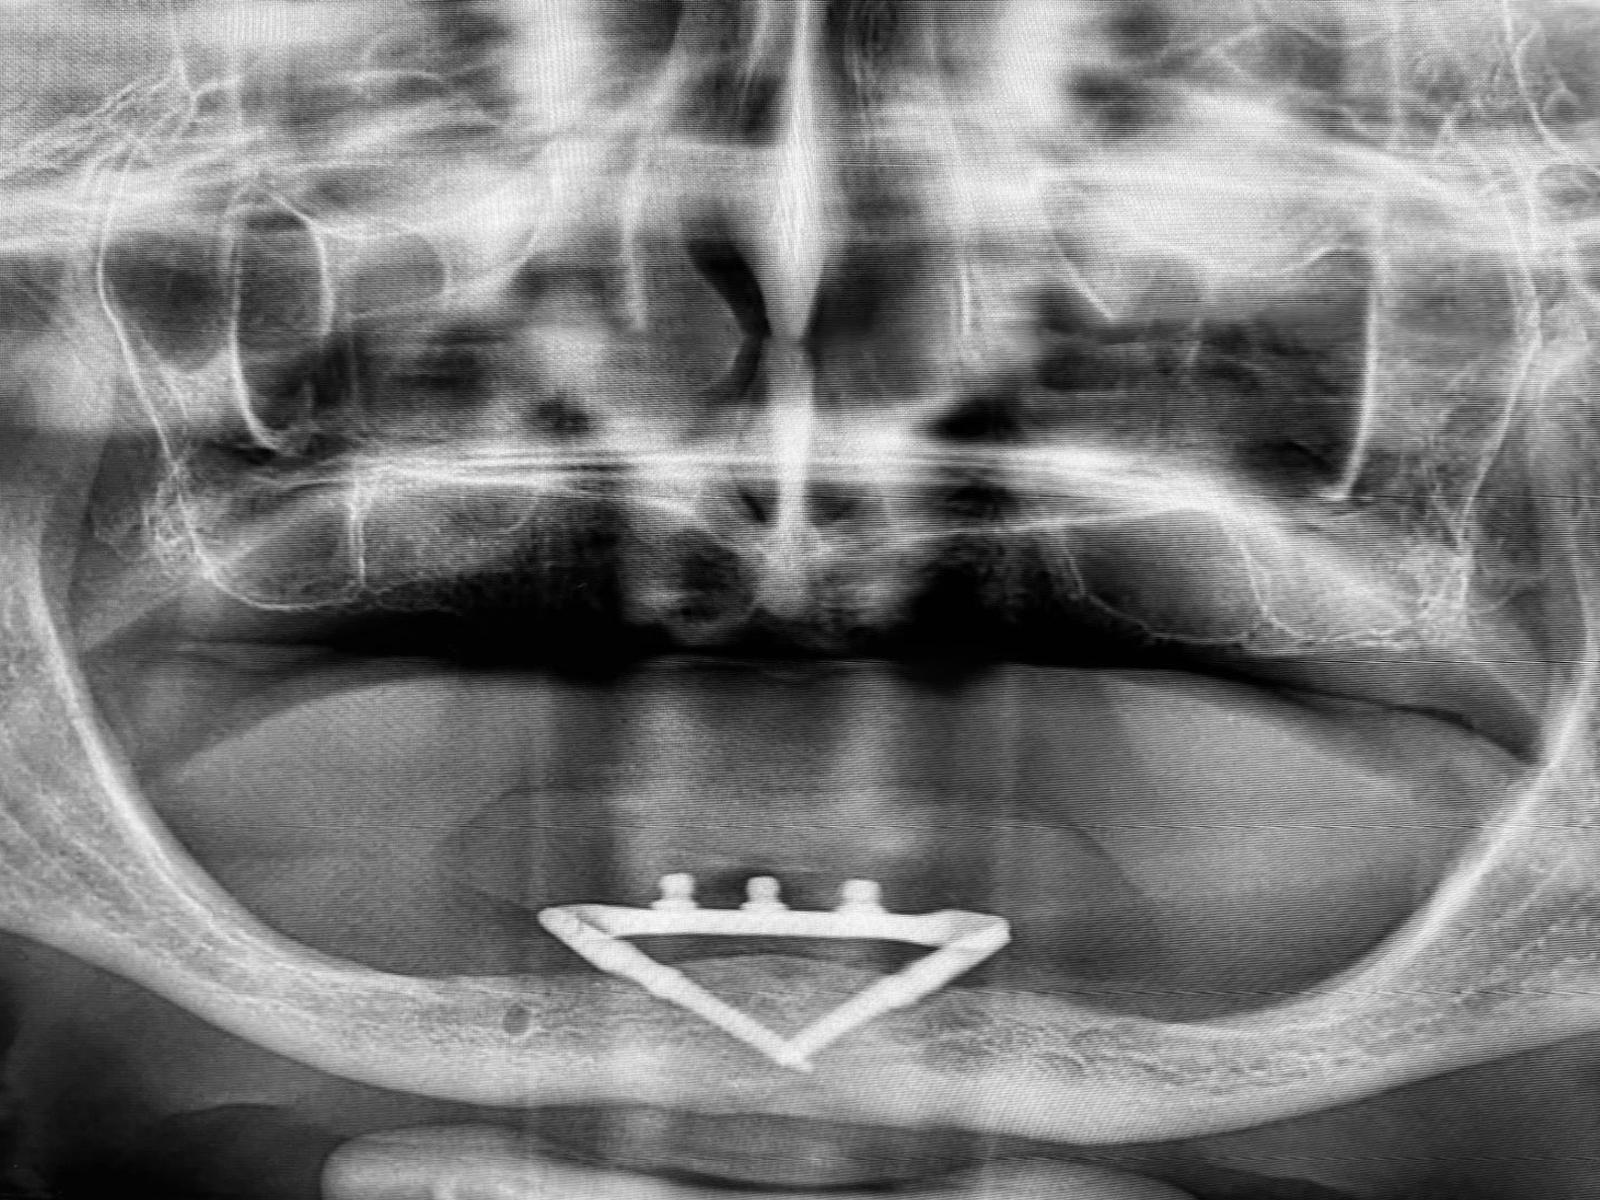

1. Fixovaný CAD/CAM subperiosteální implantát

Fixovaný subperiosteální implantát (SPI) je indikován jako ultima ratio v limitních situacích při nedostatečné nabídce kosti pro klasické implantáty, krátké implantáty, miniimplantáty nebo při nemožnosti, respektive odmítnutí navrhovaných augmentačních technik pacientem.

Fixovaný SPI v případech neřešitelných klasickými metodami nabízí dostatečnou škálu možností, jak kreativně zhotovit individuální konstrukci, která může být adekvátní alternativou k terapii klasickými implantáty v kombinaci s augmentačními technikami. Jeho zařazení do implantologického portfolia je ověřeno časem.